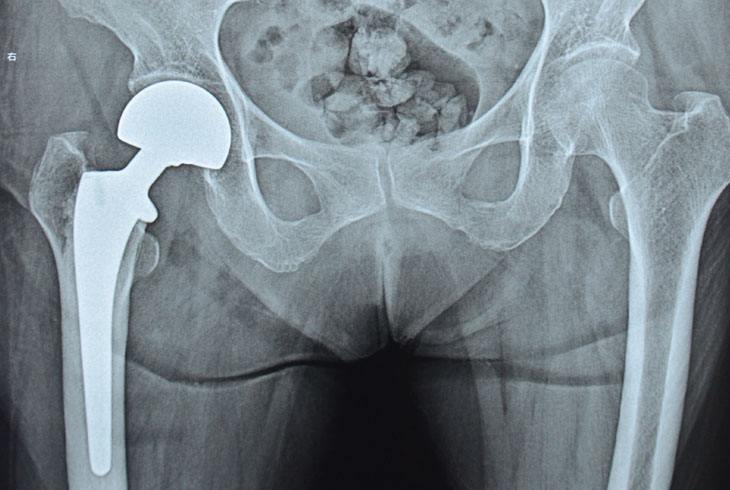

但是现在情况大不一样了,西医骨科已经有成熟的技术治疗股骨颈骨折、股骨头坏死等髋关节疾病。不管是股骨颈骨折内固定术,还是人工股骨头置换术,甚至全髋关节置换术,都是非常成熟的技术,效果也非常好。老年人术后三四天就可以在床上活动髋关节,一到两周就可以扶拐步行,三个月就基本恢复正常走路。而且,随着麻醉和护理技术的提高,八十几岁,甚至九十几岁的老人开刀已经不再是禁忌了。